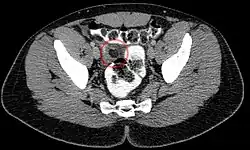

Epiploic appendagitis in computed tomography.

Abdominal CT scan, Epiploic Appendagitis (circle)

Ultrasound and CT scans are the normal means of positive diagnosis of epiploic appendagitis. Ultrasound scans show "an oval, non-compressible hyperechoic mass with a subtle hypoechoic rim directly under the site of maximum tenderness".[4] Normally, epiploic appendages cannot be seen on CT scan.[4] After cross-sectional imaging and the increased use of abdominal CT for evaluating lower abdominal pain, EA is increasingly diagnosed. Pathognomonic CT scan data represent EA as 2–4 cm, oval shaped, fat density lesions, surrounded by inflammation. Contrasting with diverticulitis findings, the colonic wall is mostly unchanged.